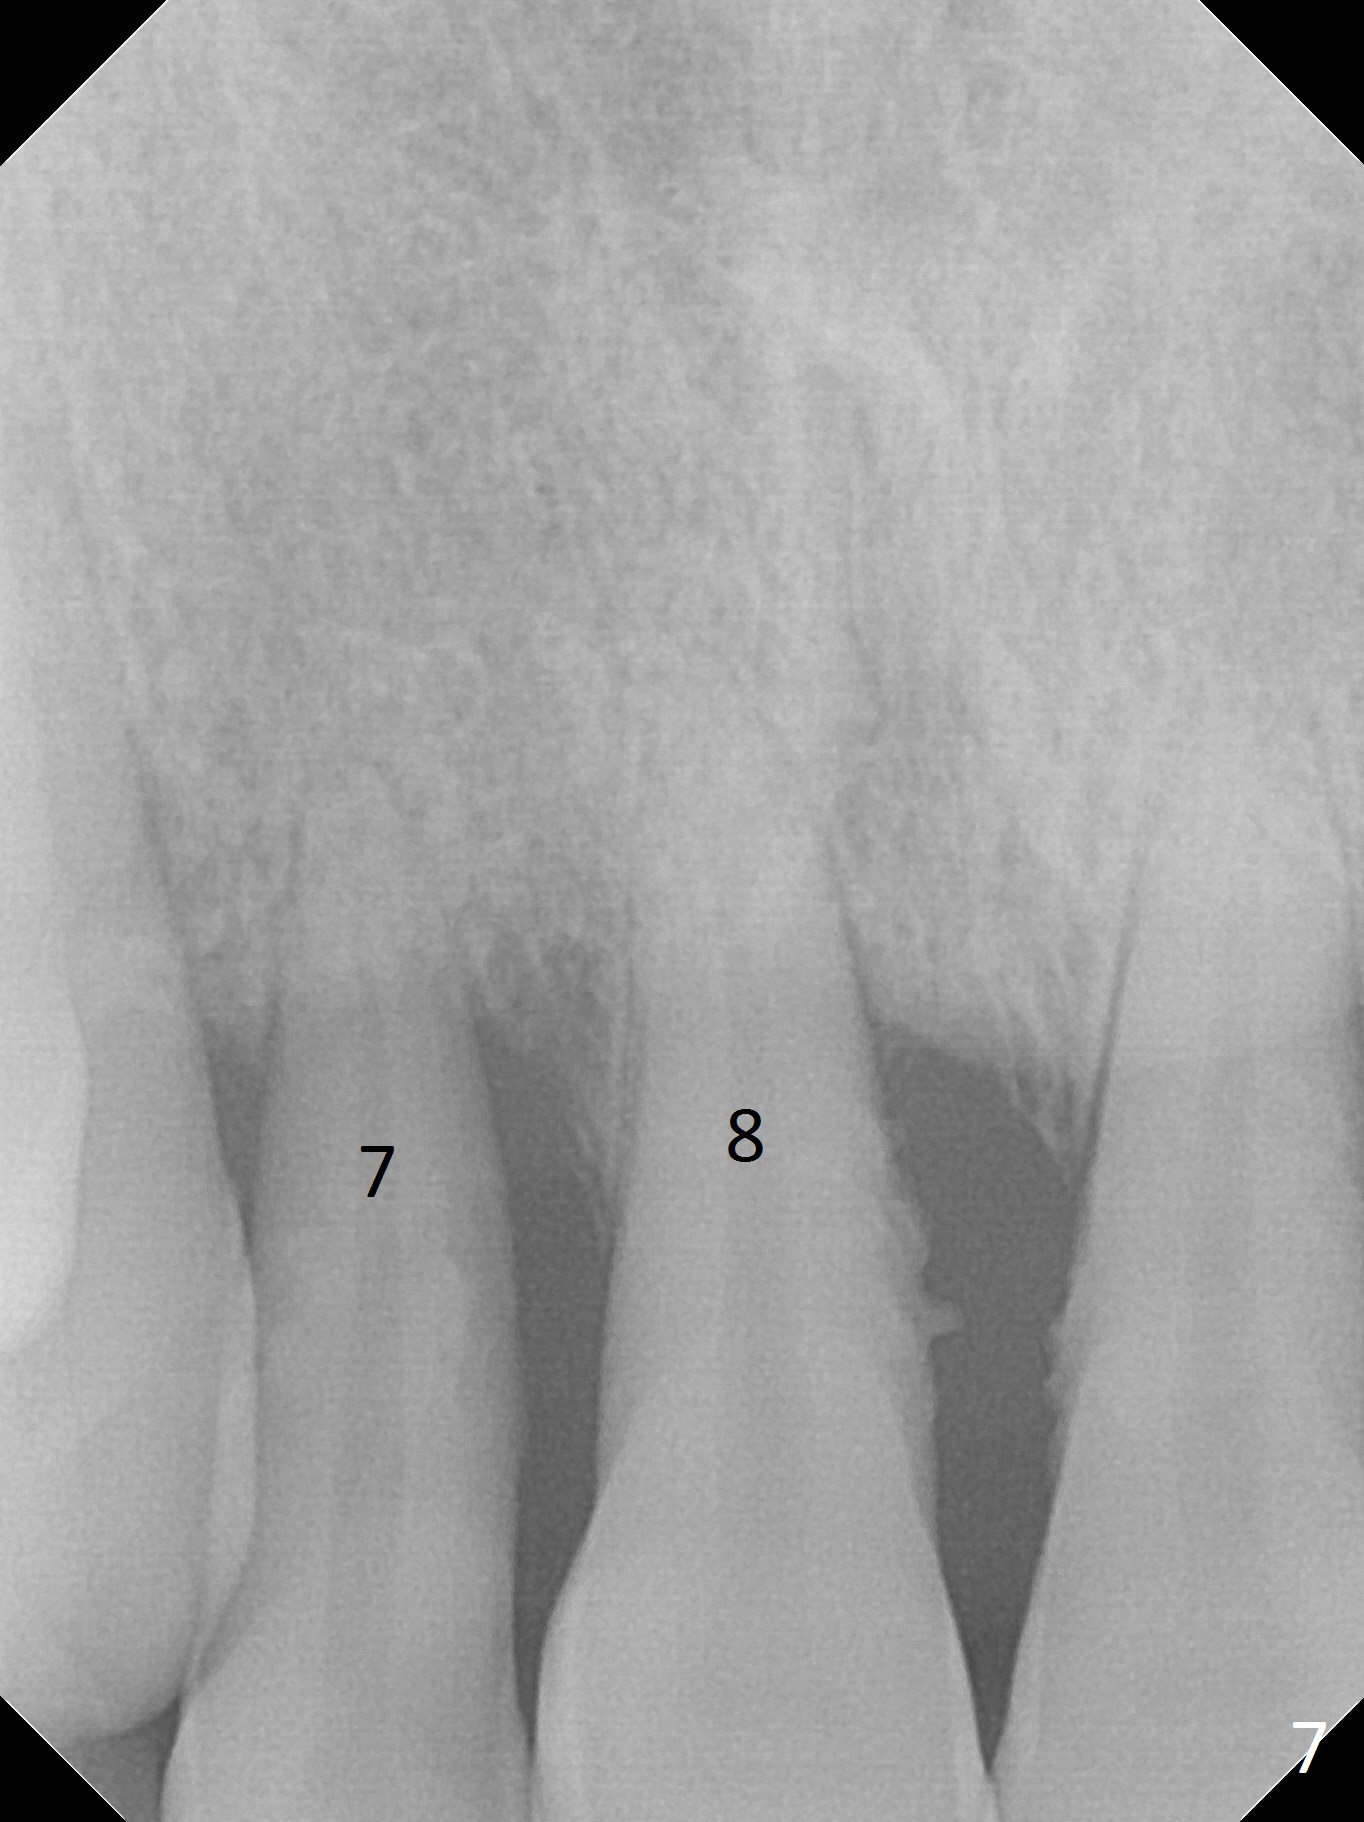

Class II Division II malocclusion (Fig.2,6) will make it difficult to restore #23-26 implant-supported FPD. Although the teeth #7-10 may need to be replaced later (Fig.7,8), enameloplasty will be conducted for #7-10 (Fig.9 white area; Fig.12 black circles (gross reduction)) prior to #23-26 extraction and implant placement (Fig.10). To be flexible in restoration (angulation) and possible future hybrid denture, 2-piece narrow implants will be placed (3.0 or 3.3 mm) instead of 1-piece ones. In fact CBCT shows that the narrowest regular implant (3.8 mm) can be placed in the lower anterior region (Fig.13-15).